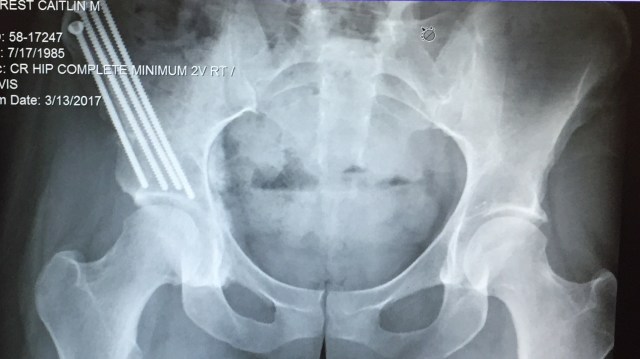

- I finally got brave enough to post my x-rays and incision pictures to social media in hopes that people would better understand what I’m going through. I think it has definitely helped and I feel grateful for having the advice given to me.

- I haven’t fallen for a couple weeks now. Yay! I’m still so bummed about the four falls I have taken. I told myself I wouldn’t be a patient that fell. I thought the people that fell must have just been careless or maybe they had a drop in blood pressure and got dizzy. Well jokes on me for judging because I have four under my belt and I’m not proud of them. I am just thankful that my screws are in place and I haven’t done any damage.

I saw my surgeon yesterday for my 6 week follow up. He said my x-rays look “beautiful” and everything is in place where it should be. He is impressed with the ROM I have in the hip, although it really hurt when he was quickly moving my leg around. He finally noticed that I was wincing and arching my back to brace myself. When he slowed the movements down they weren’t as painful. The worst is when he rolled my ankle side to side and when he brings my knee into my chest. He said it’s normal to feel uncomfortable as there was a ton of trauma in there recently and also from the screws. He wants my PT going further in the passive ROM exercises to get my body use to it since the movement is there, it’s just uncomfortable/painful.